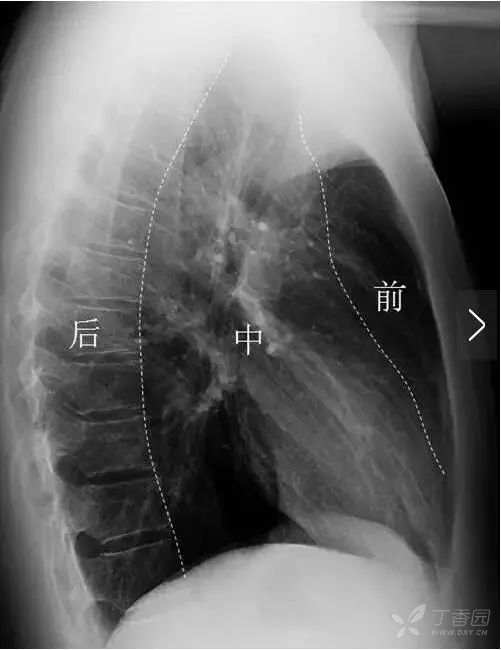

正位胸片上无法看到两肺斜裂。侧位胸片常可见两肺的斜裂(图12)。侧位片也可见水平裂(图12),起自斜裂中点附近,向前水平或稍向下达前胸壁。

图12 三角箭标示两肺斜裂,呈细线状,右肺斜裂起自第4胸椎位置,向前下斜行达横膈前部距前肋膈角约2~3 cm。左肺斜裂起点稍高于右肺,两肺的斜裂在侧位胸片上大致重合。白色箭头标示水平裂,起自斜裂中点附近,向前水平或稍向下达前胸壁 。

纵隔分区一般都是在侧位胸片上进行,分区的方法有多种,比较常用的是九分区法,即纵行画线(图14)将纵隔分为前、中、后纵隔。其中气管、升主动脉、心脏之前的区域为前纵隔;食管及食管以后、胸椎区域属于后纵隔;前、后纵隔之间为中纵隔,主要包括心脏和大血管、气管、肺门等。横向上(图15)分别自T4、T8下缘水平画水平线,可将纵隔分为上、中、下纵隔。

图14 侧位胸片纵隔纵向分区。气管、升主动脉、心脏之前的区域为前纵隔,食管及食管以后、胸椎区域属于后纵隔,前、后纵隔之间为中纵隔 。

图15 侧位胸片纵隔纵横向分区。分别自第4、8胸椎下缘水平画线,可将纵隔分为上、中、下纵隔。